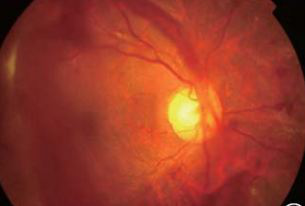

糖网的视网膜血管渗漏

早期糖网-血管瘤样改变

中期糖网血管闭塞及新(xīn)生血管形成